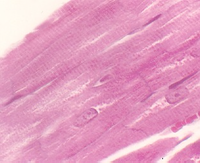

- Peripheral Nerve histology

- Touch/Position/Vibration Receptors

- Stretch receptors in skeletal muscle